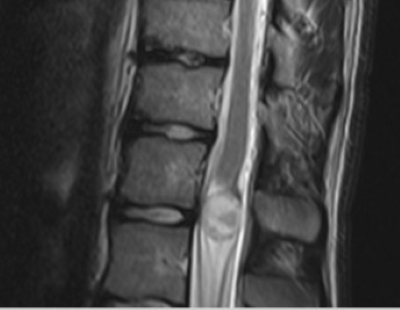

Abbildung zeigt Bilder einer MRT bei Krebs: (1) Wirbelsäulentumor, (2) Knochentumor, (3) Spinalkanaltumor, (4) Mamma-CA (Brustkrebs)

Tumorgewebe ändert die Eigenschaften des betroffenen Gewebes oder wenn es sich um gestreute Tumormetastasen handelt, stellt es sich als Fremdkörpergewebe dar mit anderen Eigenschaften als die Umgebung, die MRT stellt dies technisch als Bildveränderung sichtbar dar und lässt sich somit als Tumor diagnostizieren. Bei zusätzlichen Kontrastmittel-gestützten Bildsequenzen lässt sich zudem das abnormale Durchblutungsverhalten der Tumore erkennen: Das Kontrastmittel ist selbst deutlich als verändertes Signal der Gewebe wahrzunehmen. Tumore können entweder als zeitweise Verstärkung oder Verminderung des Bildsignals im Vergleich zum umgebenden Gewebe abgegrenzt werden.